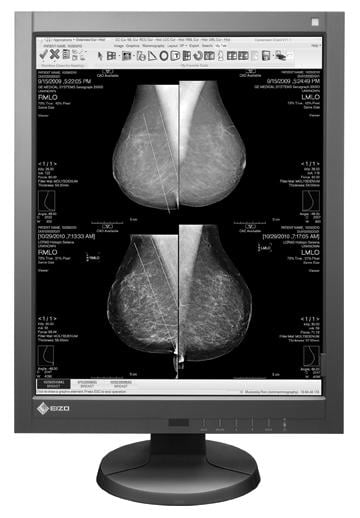

Looking for signs of cancer in the mammogram of a dense breast is like looking for a polar bear in a snowstorm. Because they absorb X-rays, glandular and fibrous tissue appear white, as do microcalcifications, lumps and other lesions that may indicate breast cancer.

The practice of breast imaging and screening in women at risk for breast cancer is evolving as new imaging modalities are incorporated and researchers continue to study the implications of dense breast tissue in patients. At the 2013 annual meeting of the Radiological Society of North America (RSNA) in Chicago, there were several sessions highlighting trials and studies that brought breast density and cancer detection to the forefront.